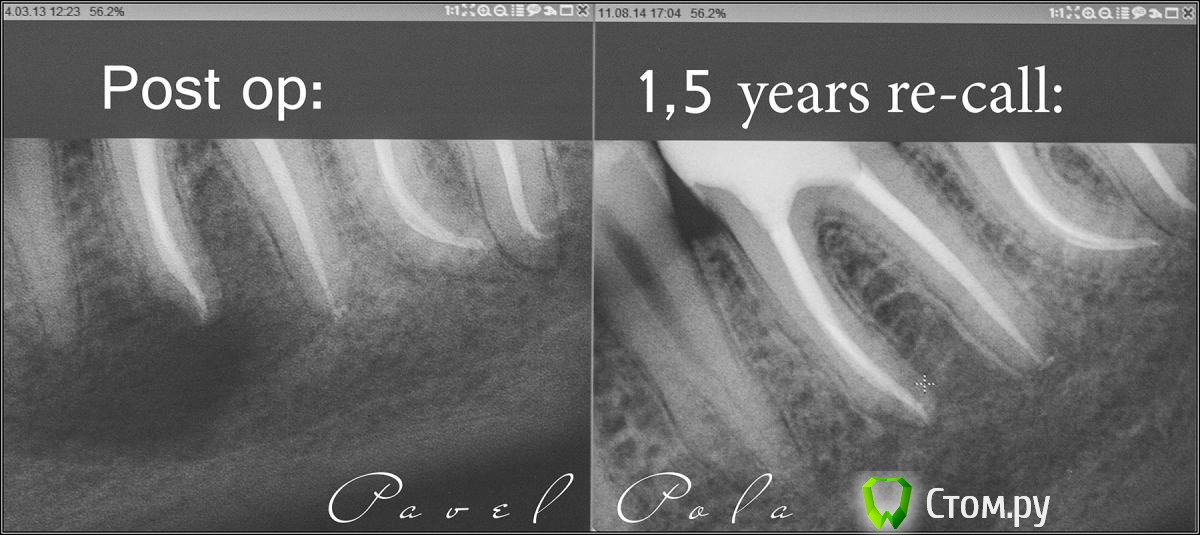

M@estro Опубликовано 11 августа, 2014 Автор Поделиться Опубликовано 11 августа, 2014 (изменено) Я выкладывал промежуточные "ре - колл" этого пациента , вот сегодняшний : http://s019.radikal.ru/i618/1408/8a/599ad8b5f3ea.jpg из разряда - " когда зав. отделением говорит "удаляй" . Изменено 11 августа, 2014 пользователем M@estro 10 Ссылка на комментарий